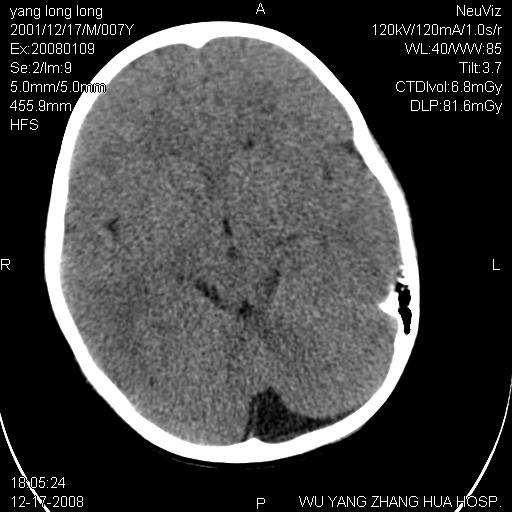

标题: PED1686:M7Y,头外伤,家人及自诉平时无任何不适。 [打印本页]

标题: PED1686:M7Y,头外伤,家人及自诉平时无任何不适。

考虑蛛网膜囊肿,请老师们看看多指导指导。

多考虑大枕大池。本例颅骨歪歪的,灶后枕骨似有膨胀征像(为蛛网膜囊肿征像),但整个左侧枕叶后方枕骨均有向后膨隆,所以暂不考虑蛛网膜囊肿。必要时随访

鉴别巨大枕大池与蛛网膜囊肿之间,倾向前者。

病变向两侧延伸,颅骨内板受压侵蚀,似有张力!!还是考虑蛛网膜囊肿!!